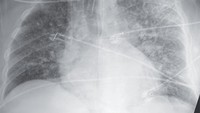

Pasien pertama mengeluhkan mual, muntah, rasa haus berlebihan, ketidaknyamanan perut, nyeri punggung, dan demam. Dokter menemukan cairan menumpuk di paru-parunya yang membuatnya bernapas dengan cepat dan kadar oksigen yang menurun. (Foto: New England Journal of Medicine)